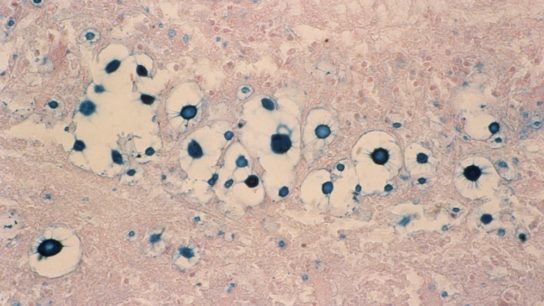

While immunocompromised patients are the most susceptible to CNS fungal infections, they can also occur in immunocompetent patients undergoing invasive procedures such as neurosurgery and in patients exposed to contaminated devices or drugs.